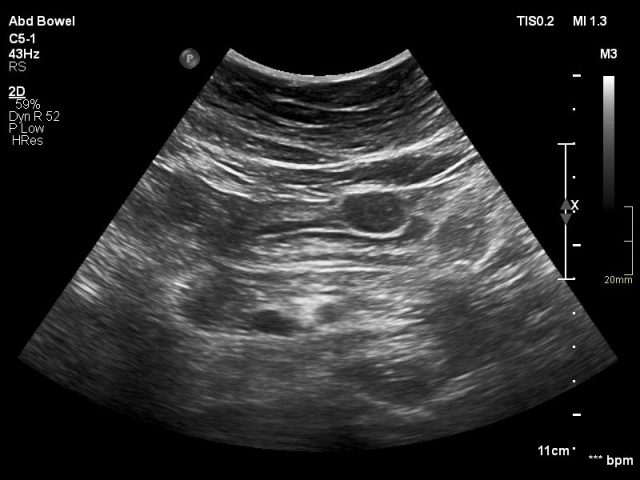

The small bowel is attached to the mesentery which is folded like a fan.

The mesentery contains a variable amount of fat, and the folded, fatty mesentery has a multi-layered aspect, especially when compressed during US.

The normal mesentery (arrows)  in thin patients is only visible when there is ascites.

In the obese, the mesentery contains a lot of fat and can be visualized as a well-compressible, flat, multi-layered structure.

In one plane this may simulate a thickened bowel wall (arrows in left image) .

Turning the probe 90 degrees (right image), it is immediately recognized as a flat structure (arrows).